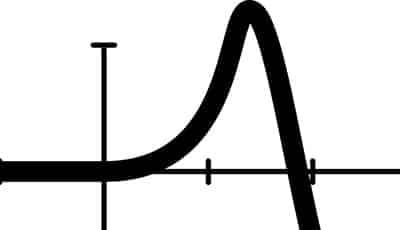

- Het maximale aantal toegestane carpules LA-vloeistof is afhankelijk van het type lokaal analgeticum en de leeftijd (gewicht) van de patiënt. Zo is de maximale hoeveelheid ultracain bij een driejarig kind 2¼ carpules en bij een kind van zeven jaar is dit 3¼ carpules. Doorgaans is bij een normale behandeling een halve carpule echter al voldoende.